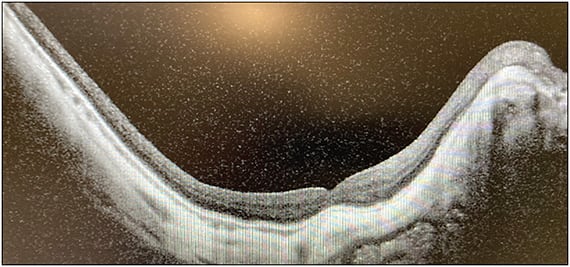

I was able to reach the macula with combination of Flex Loop and myopic forceps. I didn’t think it was helpful to use ILM as a flap because it was not quite continuous. I extended the peel even more broadly to the arcades and little past those. I did a fluid–air exchange and filled the eye with gas. I choose gas for these cases over silicone oil because I have had patients who are very myopic and silicone oil does not quite tamponade, and with the staphyloma, there might be a pocket of fluid in between that silicone oil and the retina. I’ve also found that longer-acting gas and 1 week of positioning has helped closure of myopic holes. For this patient, the OCT image taken 1 week after surgery through a gas-filled eye showed that the hole had closed (Figure 2).

Dr. Murray: That’s a beautiful picture. None of us suture anymore, but this is a case where you really need to think about suturing the myopic sites, or you can have lots of gas with underfill. At 1 week for me with that eye, I would not make my patient continue face down any longer with documentation of hole closure. Many of us aren’t keeping our patients face down even for a week, but in a complex eye like this, I would have told the patient to be face down religiously for a week and that would have been the best news I would share with the patient when I was able to see that OCT image.

Dr. Vajzovic: Yes, I had the patient do exactly 1 week of face-down positioning, primarily because this is the fifth surgery, with long-acting gas, and I wanted to make sure that we did everything possible. And at 1 week imaging I was able to share with the patient the excitement that we’re seeing it close, hopefully. We will have to see what happens when the gas is gone, but there is still pretty good fill in the eye, also.